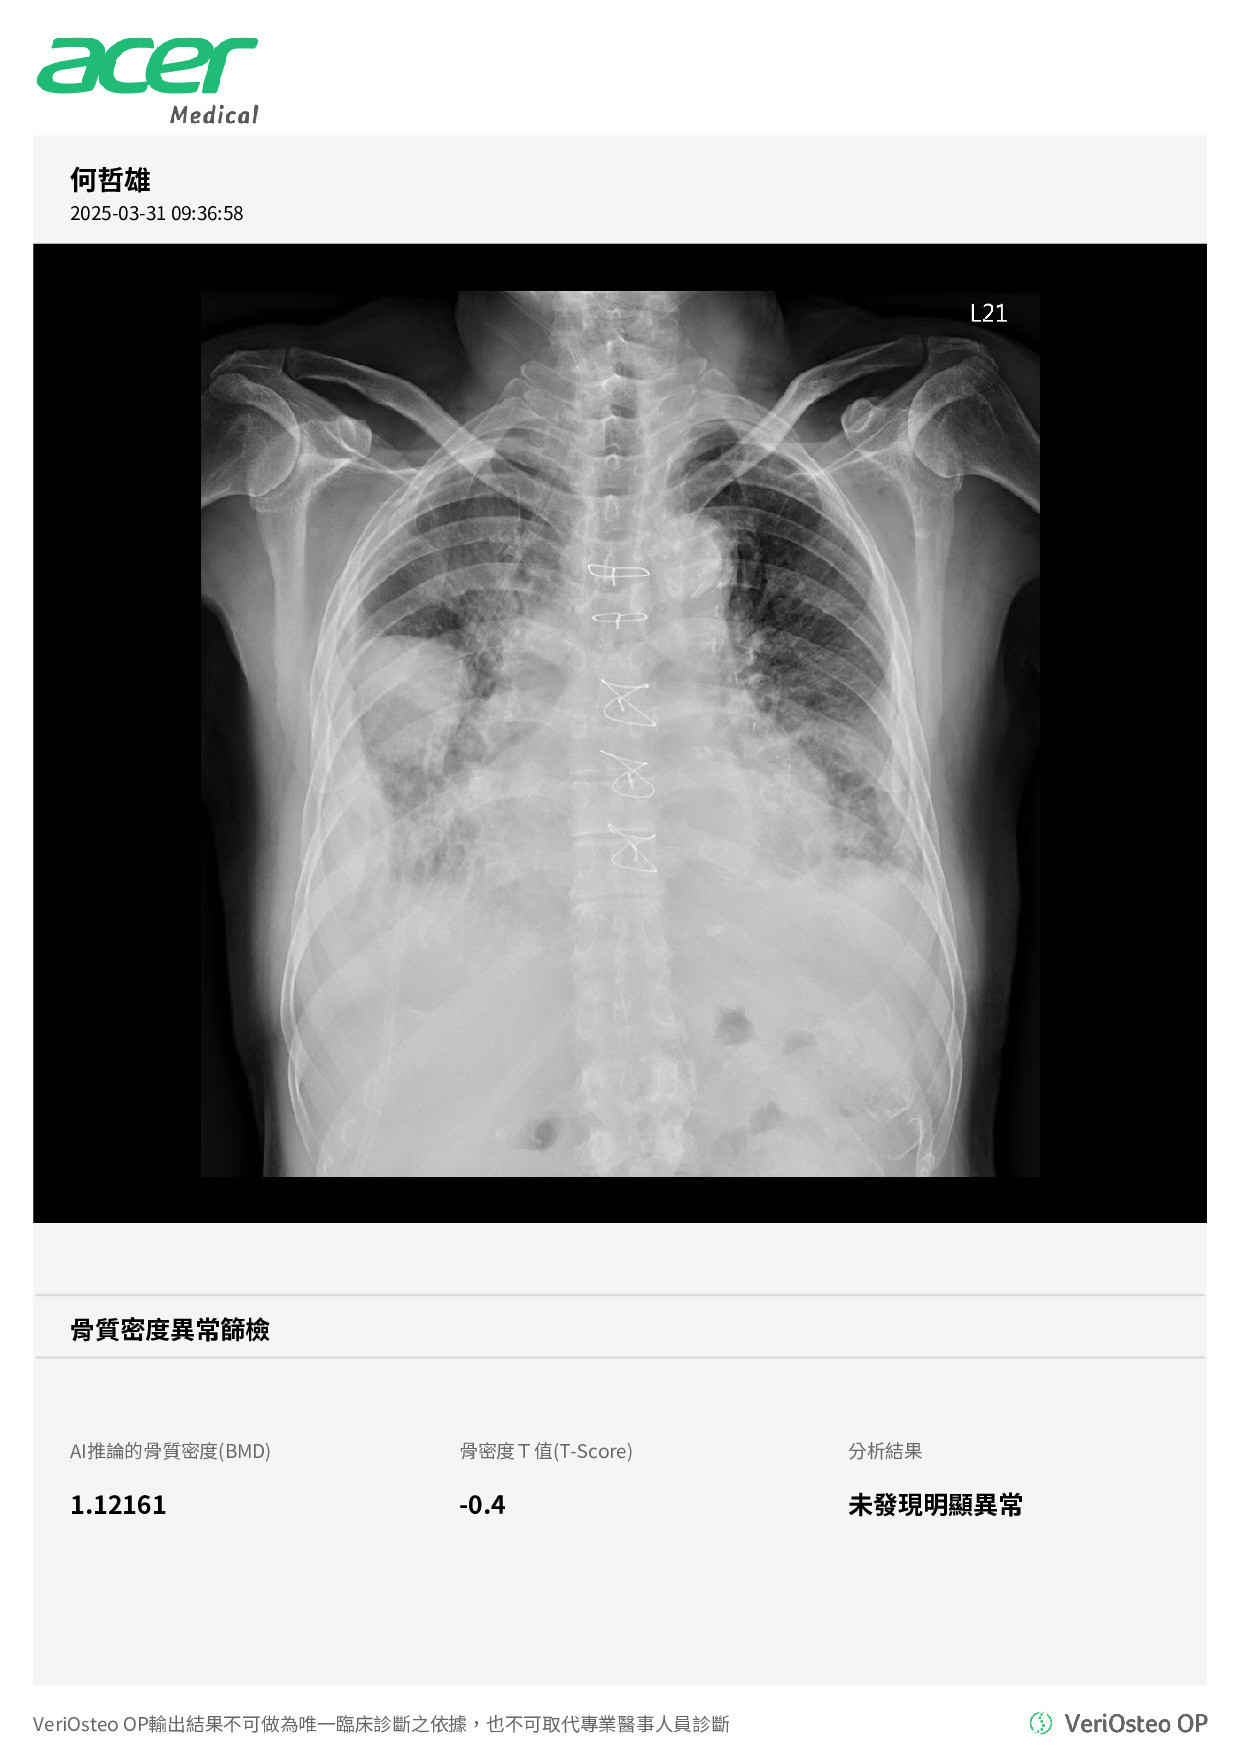

This 81 years old man with past history of (1)Congestive heart failure (ejaction fraction 26%) (2) Coronary artery disease(CAD) s/p CAB-G in 2012 (3) Chronic kidney disease (4) type 2 DM (5)Empyema s/p therapy with stasis pleural effusion . He was just discharged from our CV ward due to acute decompensated heart failure (ADHF) c/w acute pulmonary edema. This time, he was admitted due to recurrent heart failure with elevated cardiac enzyme level suspected ADHF recurrent and NSTE-ACS.

Relevant Test Results Prior to Catheterization

The LAB data showed elevated cardiac enzyme: CPK peak 641 CKMB 31 Troponin-T 1935, with poor renal function (eGFR around 20-30 ). CXR showed pulmonary edema, and right lower lobe stasis inter-lobar pleural effusion.